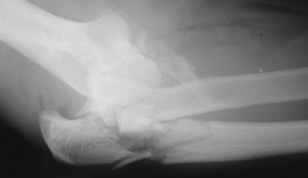

A complete elbow dislocation.

A simple dislocation does not have any major bone injury.

A complex dislocation of the elbow. In addition to dislocation, there are multiple fractures of the elbow.

In a complex elbow dislocation, surgery may be necessary to restore bone alignment and repair ligaments. It can be difficult to realign a complex elbow dislocation and to keep the joint in line.